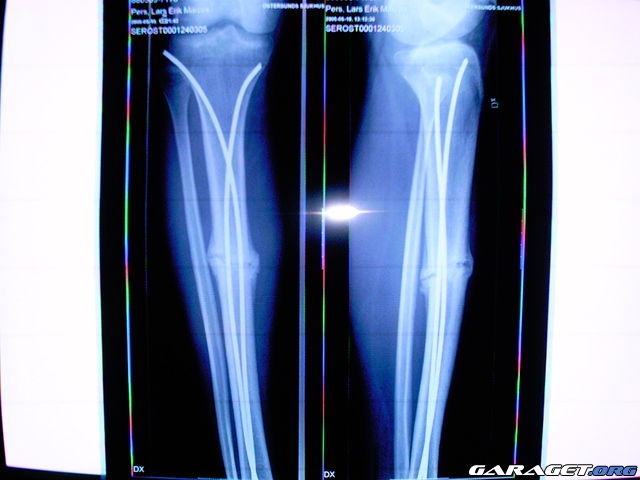

http://www.garaget.org/gallery/archive/38603/20000/38603-114066.jpg

Ett ben mellan två snöskotrar gav runt 60 000.